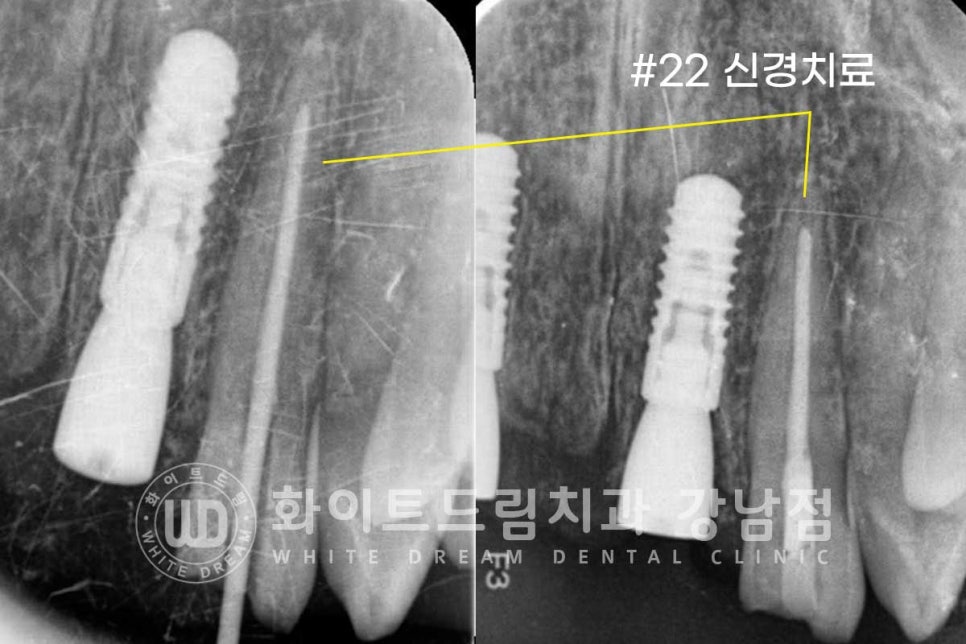

▲ 임플란트 식립 후 신경치료 진행

환자분은 스트라우만 임플란트로 치료를 받으셨는데요.

환자분은 식립 후 4개월의 회복 기간을 가졌고

원내에서 제작된 임플란트 브릿지와 22번 크라운 동시 세팅했습니다.